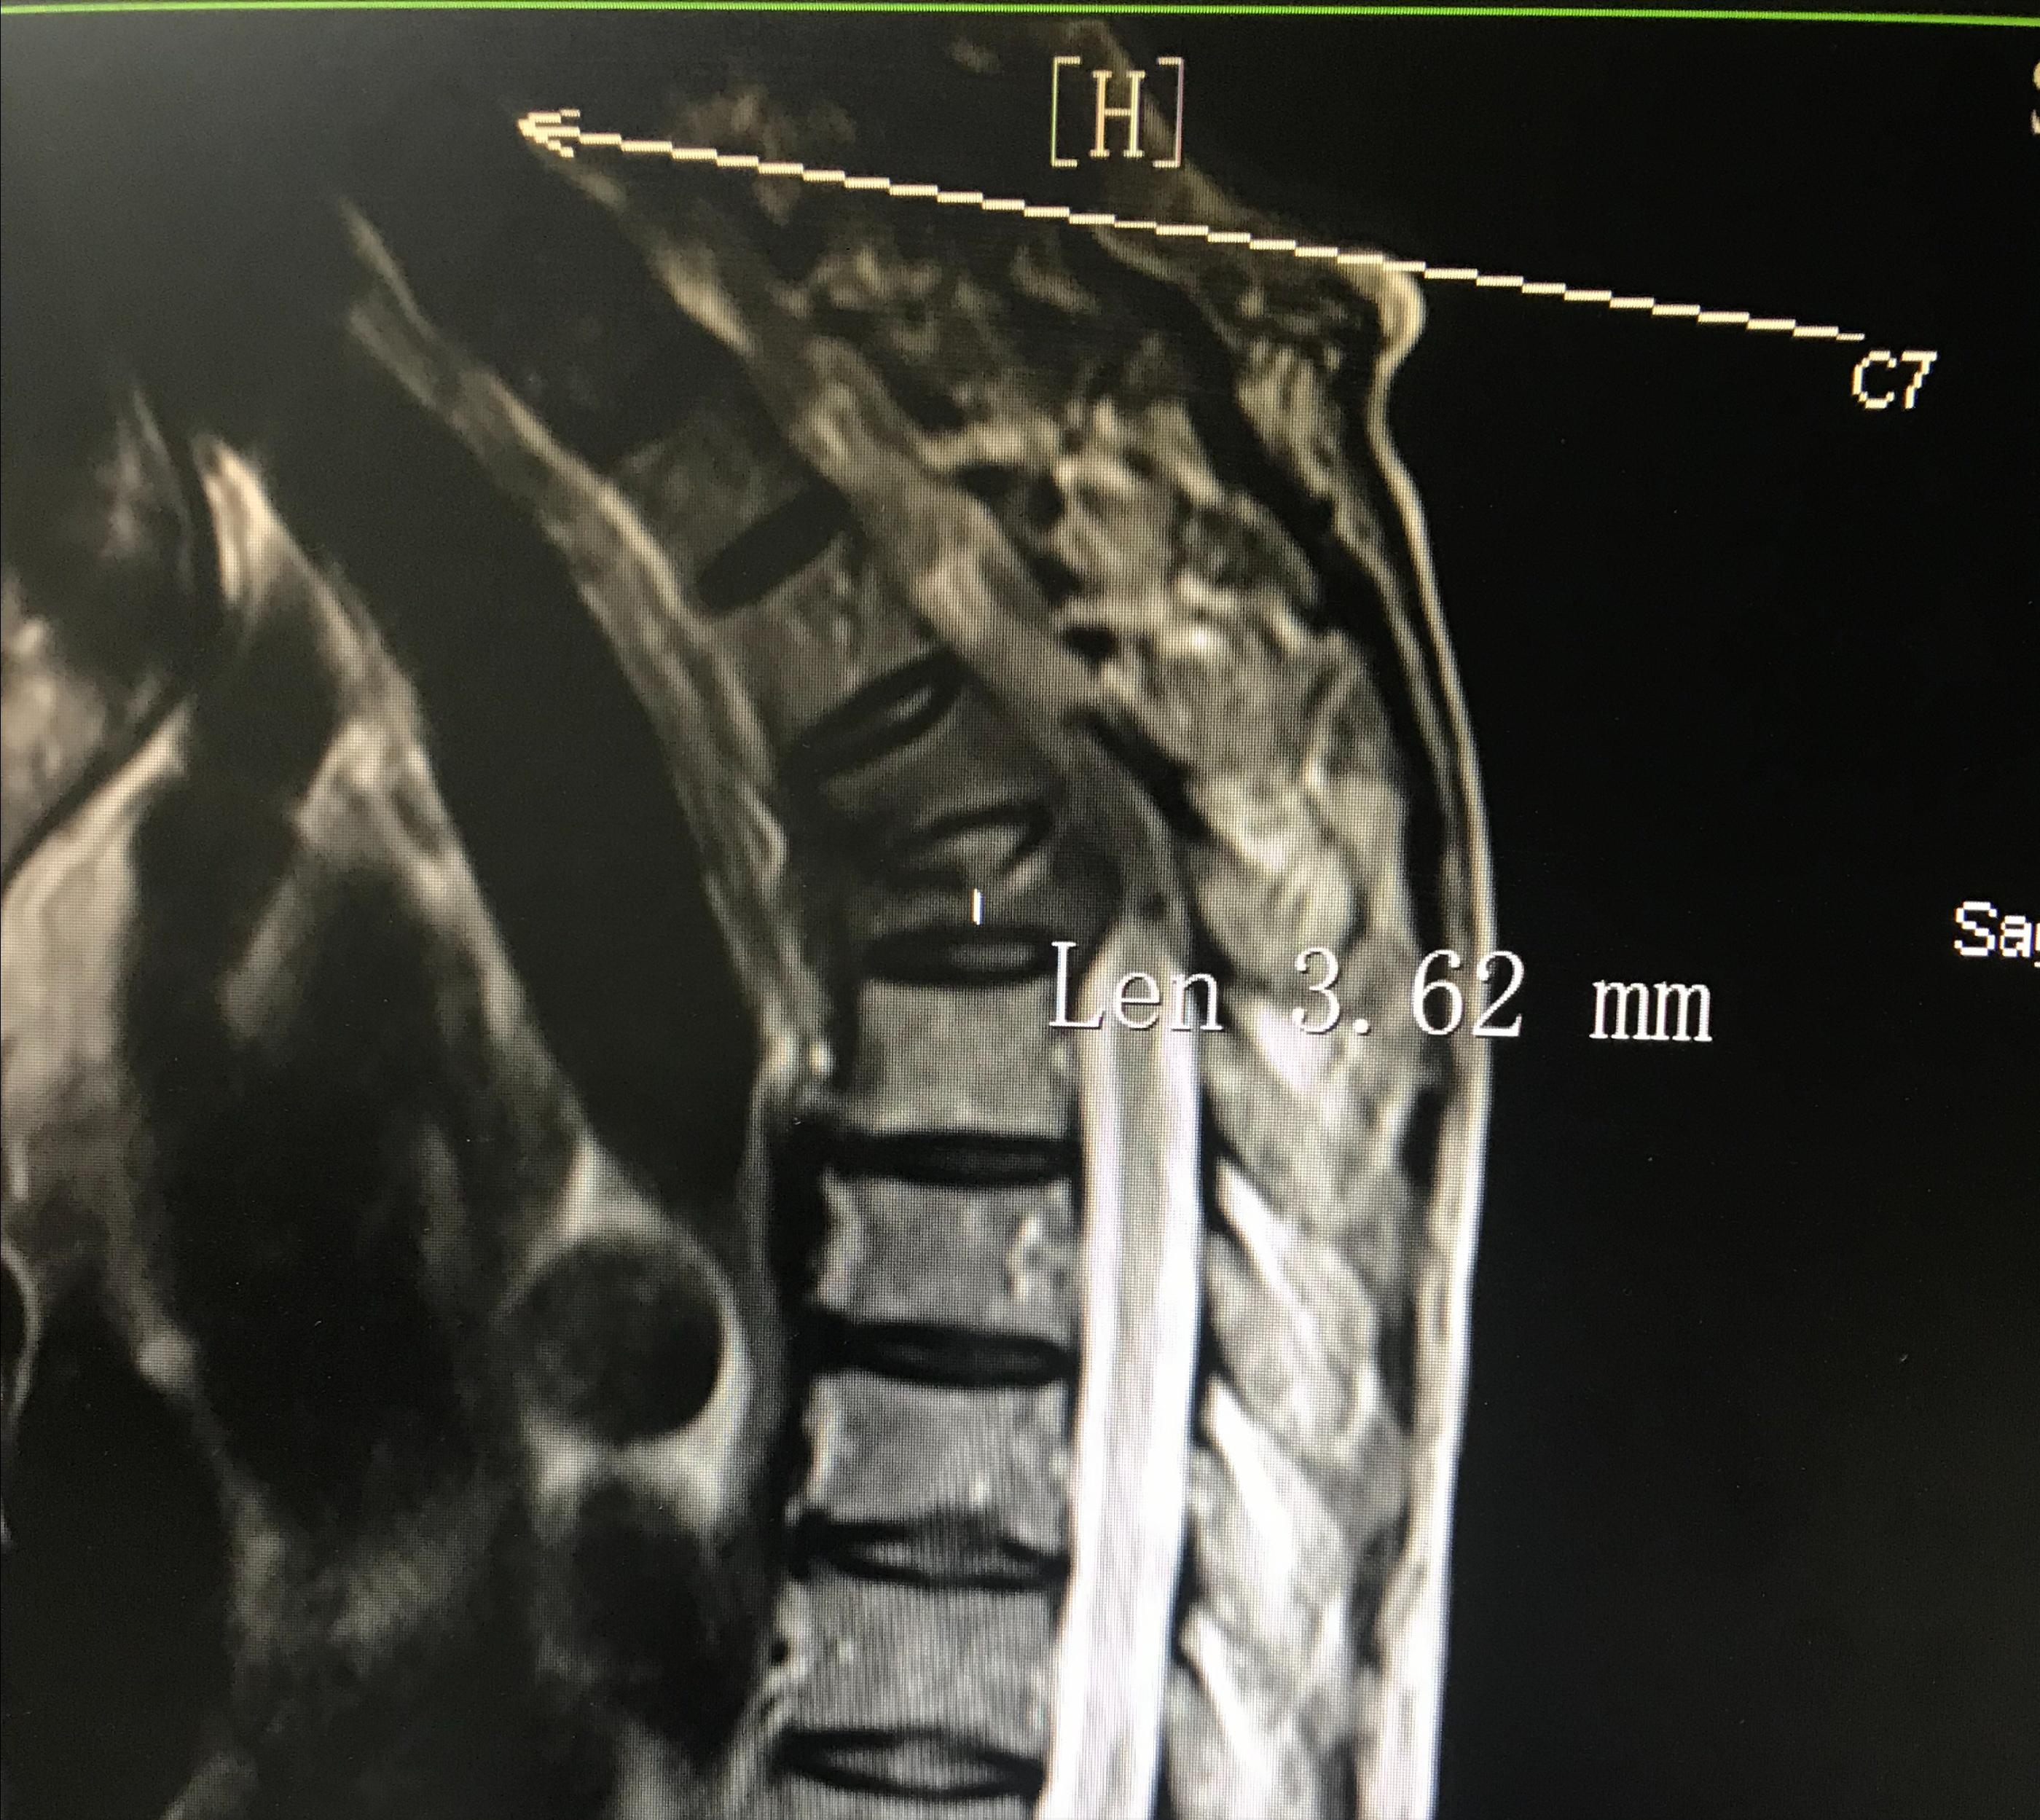

2022-11-14,行经皮穿刺DSA引导下"T5"椎体射频消融术+经皮椎体成形术(PVP),因"T5"椎体骨质肿瘤破坏并严重病理性压缩骨折,高度仅有3.62mm,而骨穿针的直径为2mm,故穿刺置针操作难度系数极高。

T5椎体转移瘤、重度压缩性骨折